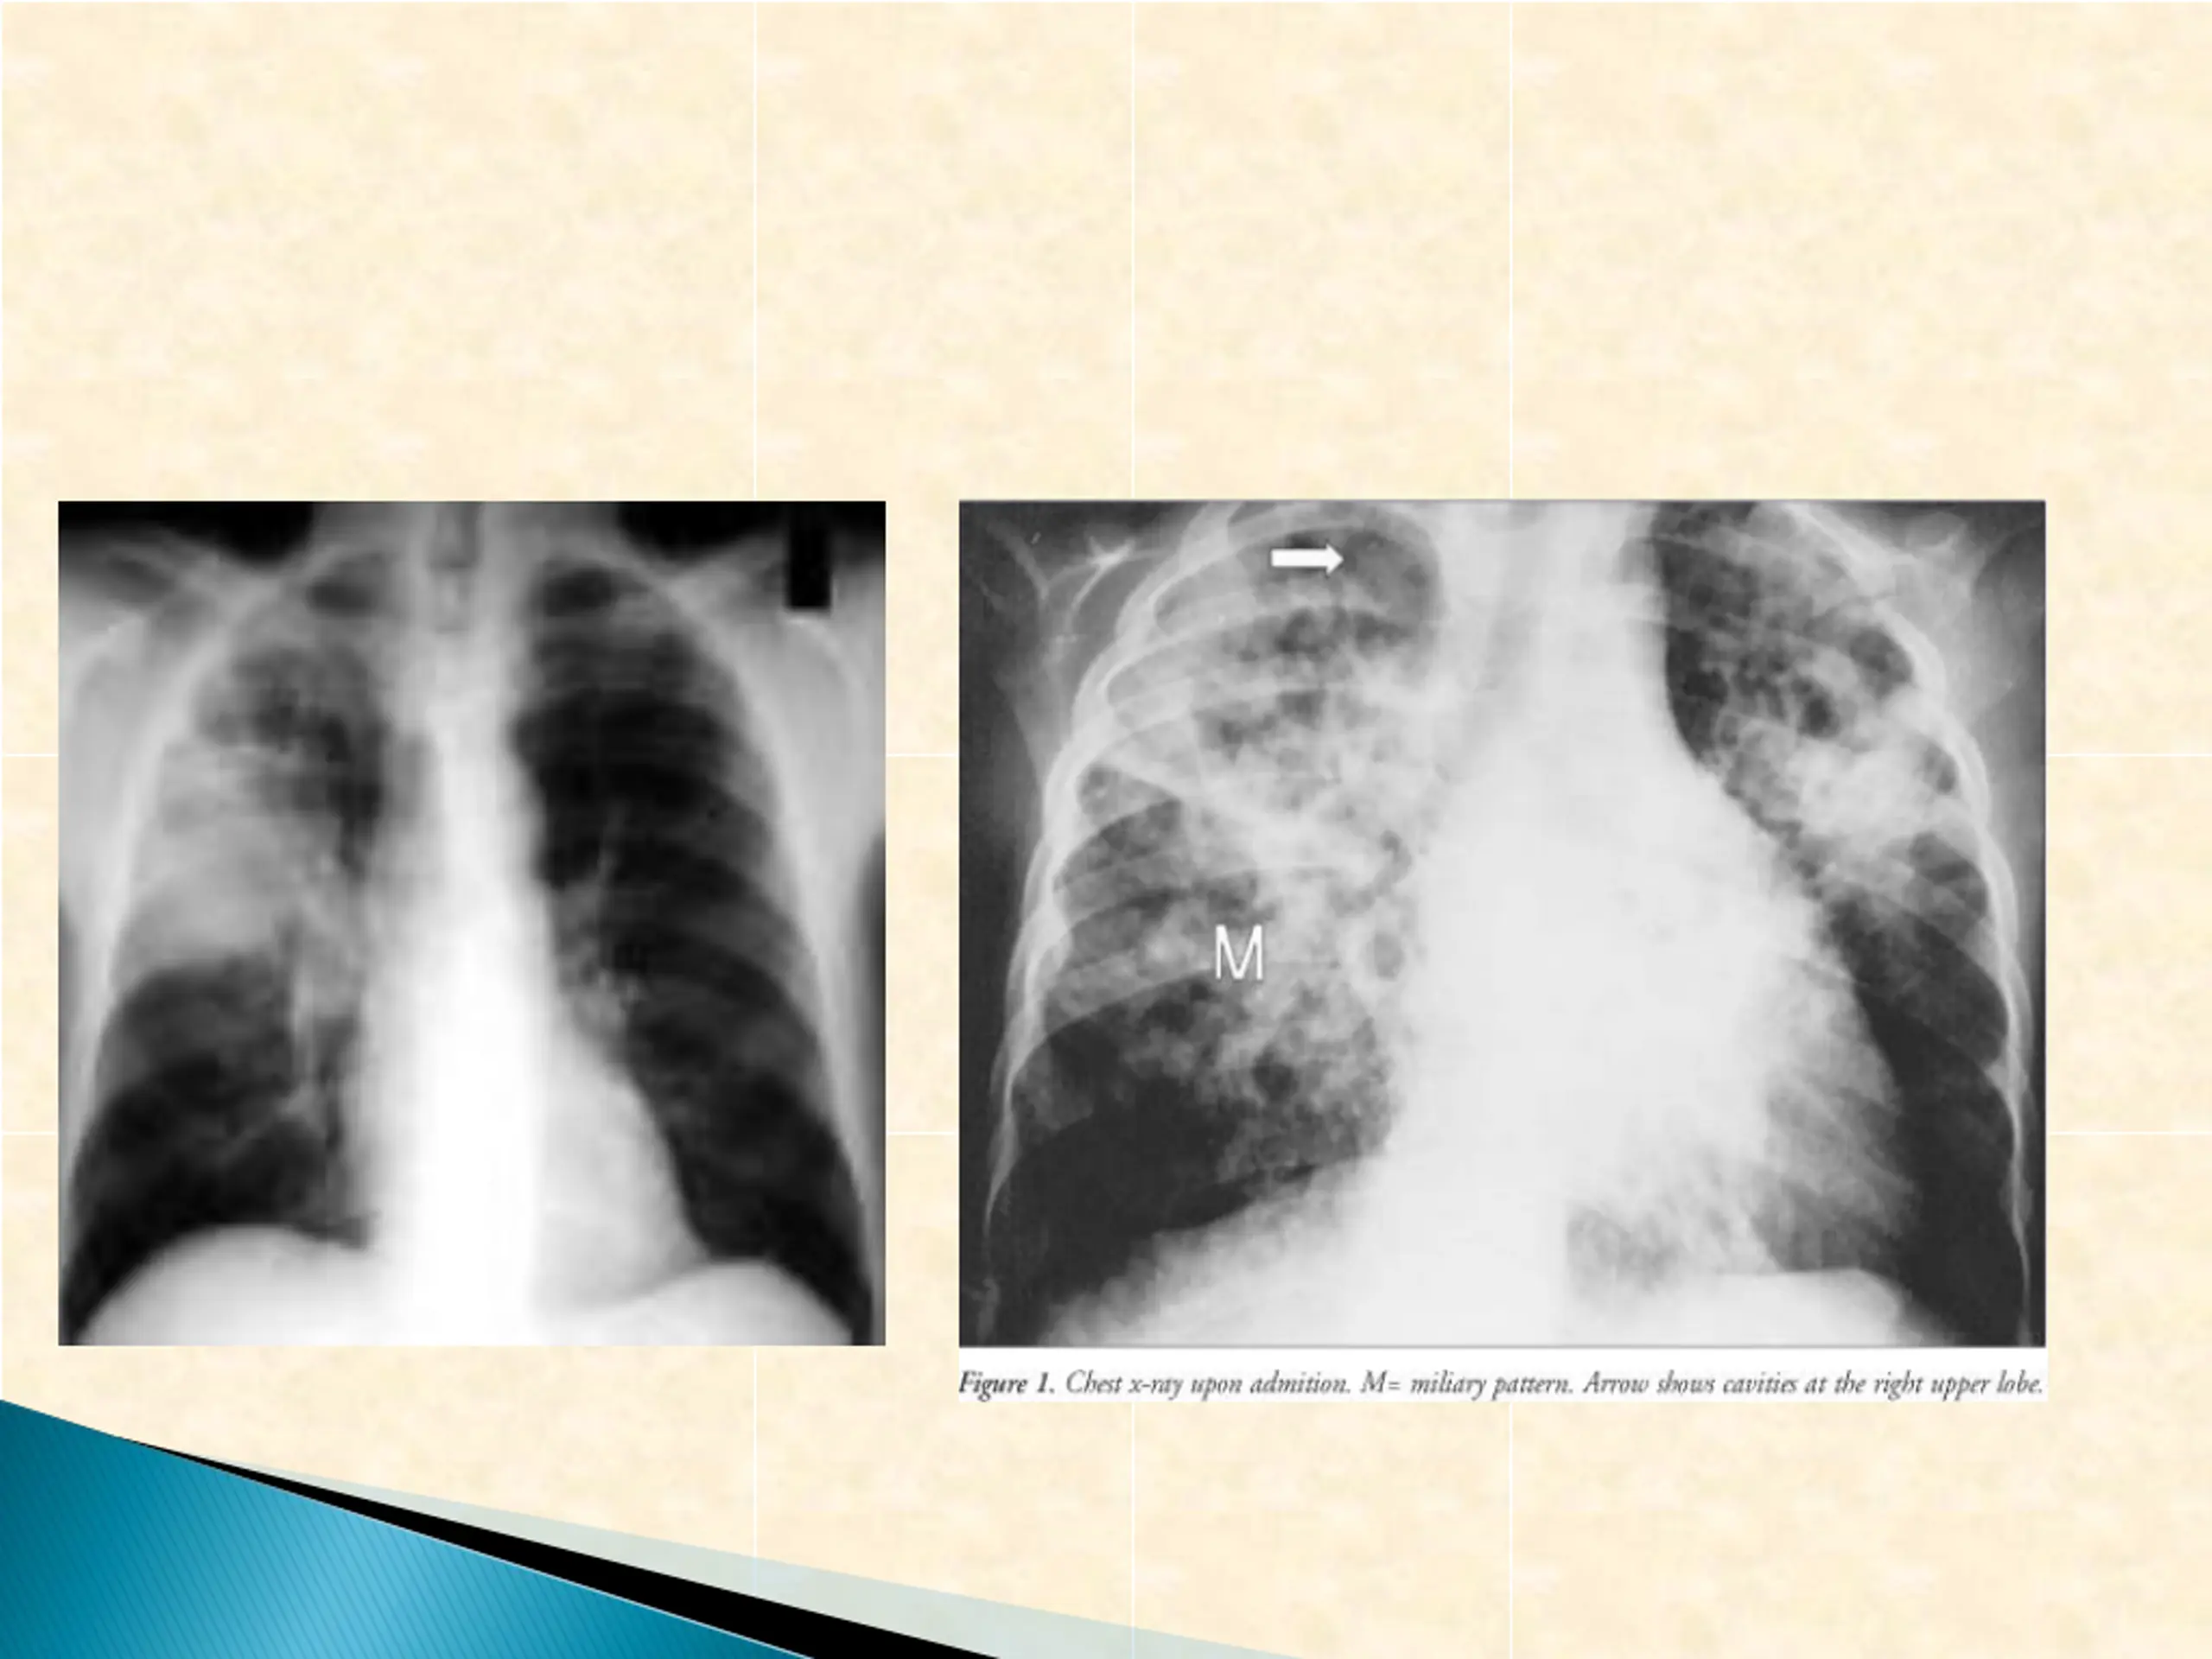

Is caused by Mycobacterium tuberculosis and other memebers of the tb complex M. tuberculosis infect one third of human race The patient usually presents with fever of long duration Symptoms of cough and coughing of blood (Haemoptoysis) when the chest is affected In some cases it present as meningitis and cerebral infection presenting with chronic neurological symptoms and signs

a) Mantoux test, Tuberculin skin test(TST) b)Chest x-ray for focus of tb infection c) CSF microscopy for AFB d) CSF culture an solid medium [L.J ]or fluid medium[MIGT] e) PCR or other molecular bioLOGY tests for presence of bacterial element tb and others f) Culture of CSF for Brucella g) Serology for Brucella Combination of these finding with clinical history and examination finding